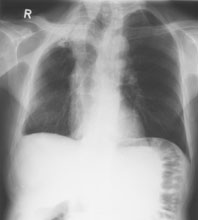

Ein 71-jähriger Italiener beklagt sich über einen reduzierten Allgemeinzustand und subfebrile Temperaturen. Er raucht seit 45 Jahren.

Husten und Auswurf hätte er immer gehabt, berichtet der Patient. Mit der Frage nach einem Infiltrat wird ein Röntgenbild verordnet:

Thorax pa

Bild vergrössern

Welche Befunde imponieren (mehrere richtige Antworten möglich)?